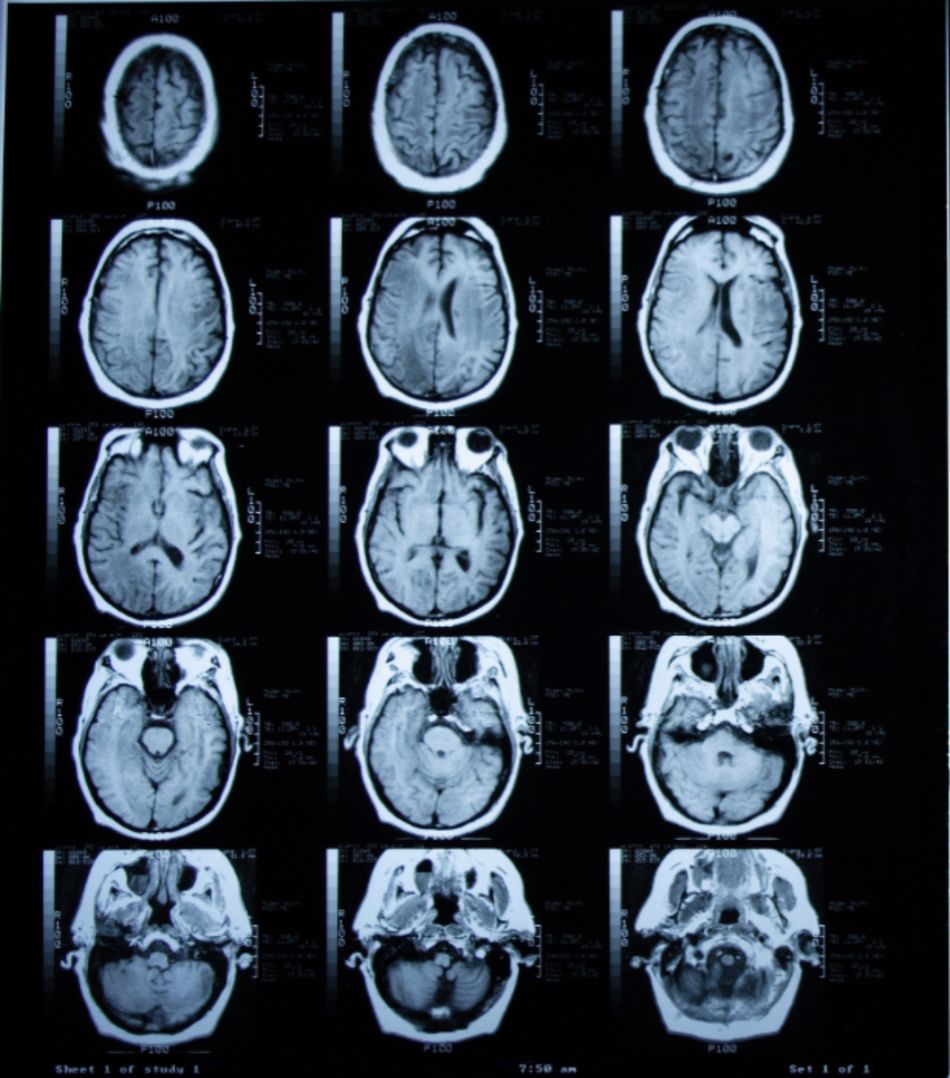

(16/26) MRT Schädel in Transversalebene, T₁‐gewichtet, FFE – DocCheck MRT Knie – DocCheck

MRT Schädel – DocCheck MRT Bild, könnte das ein Tumor sein? Kennt sich jemand damit aus? Könnte die helle Fläche ein …

MRT Schädel – DocCheck Sichere Prostatavorsorge mittels MRT-Untersuchung der Prostata

(11/26) MRT Schädel in Transversalebene, T₁‐gewichtet, FFE – DocCheck MS Herd MRT (1) – DocCheck

(16/34) MRT Schädel in Sagittalebene, T₂‐gewichtet – DocCheck MRT Bilder-Hubbel-??? Hilfe (Kopf)

MRT Schädel – DocCheck #MRT: Sungai Buloh – Kajang Line Phase 1 To Officially Start 16th December – Hype Malaysia

MRT 4 Schädel – DocCheck Taipei MRT Roadmap